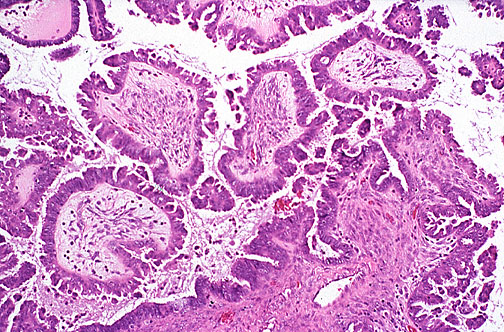

Here is a serous cystadenocarcinoma in which there is more pronounced papillary growth with more hyperchromatic cells.